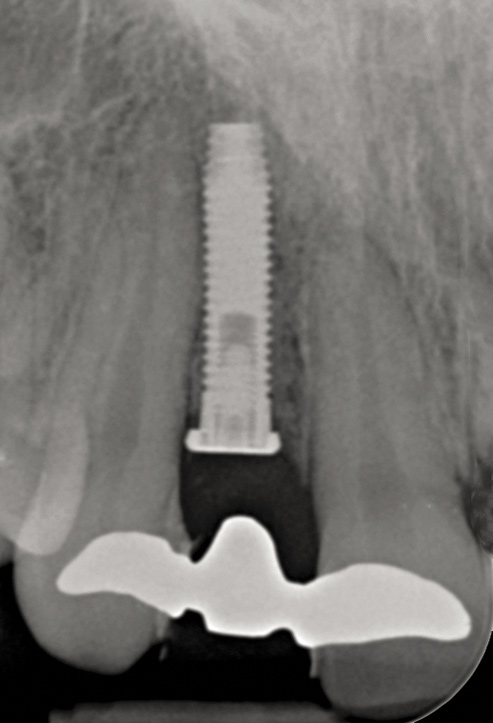

Fig 45. The definitive crown tooth No. 26 seated in place and provisionally cemented. The recession defect was eliminated with the removal and replacement of a new implant in the proper position.

Figure 45

Fig 46. The post-treatment radiograph showing a healthy stable implant and restoration.

Figure 46